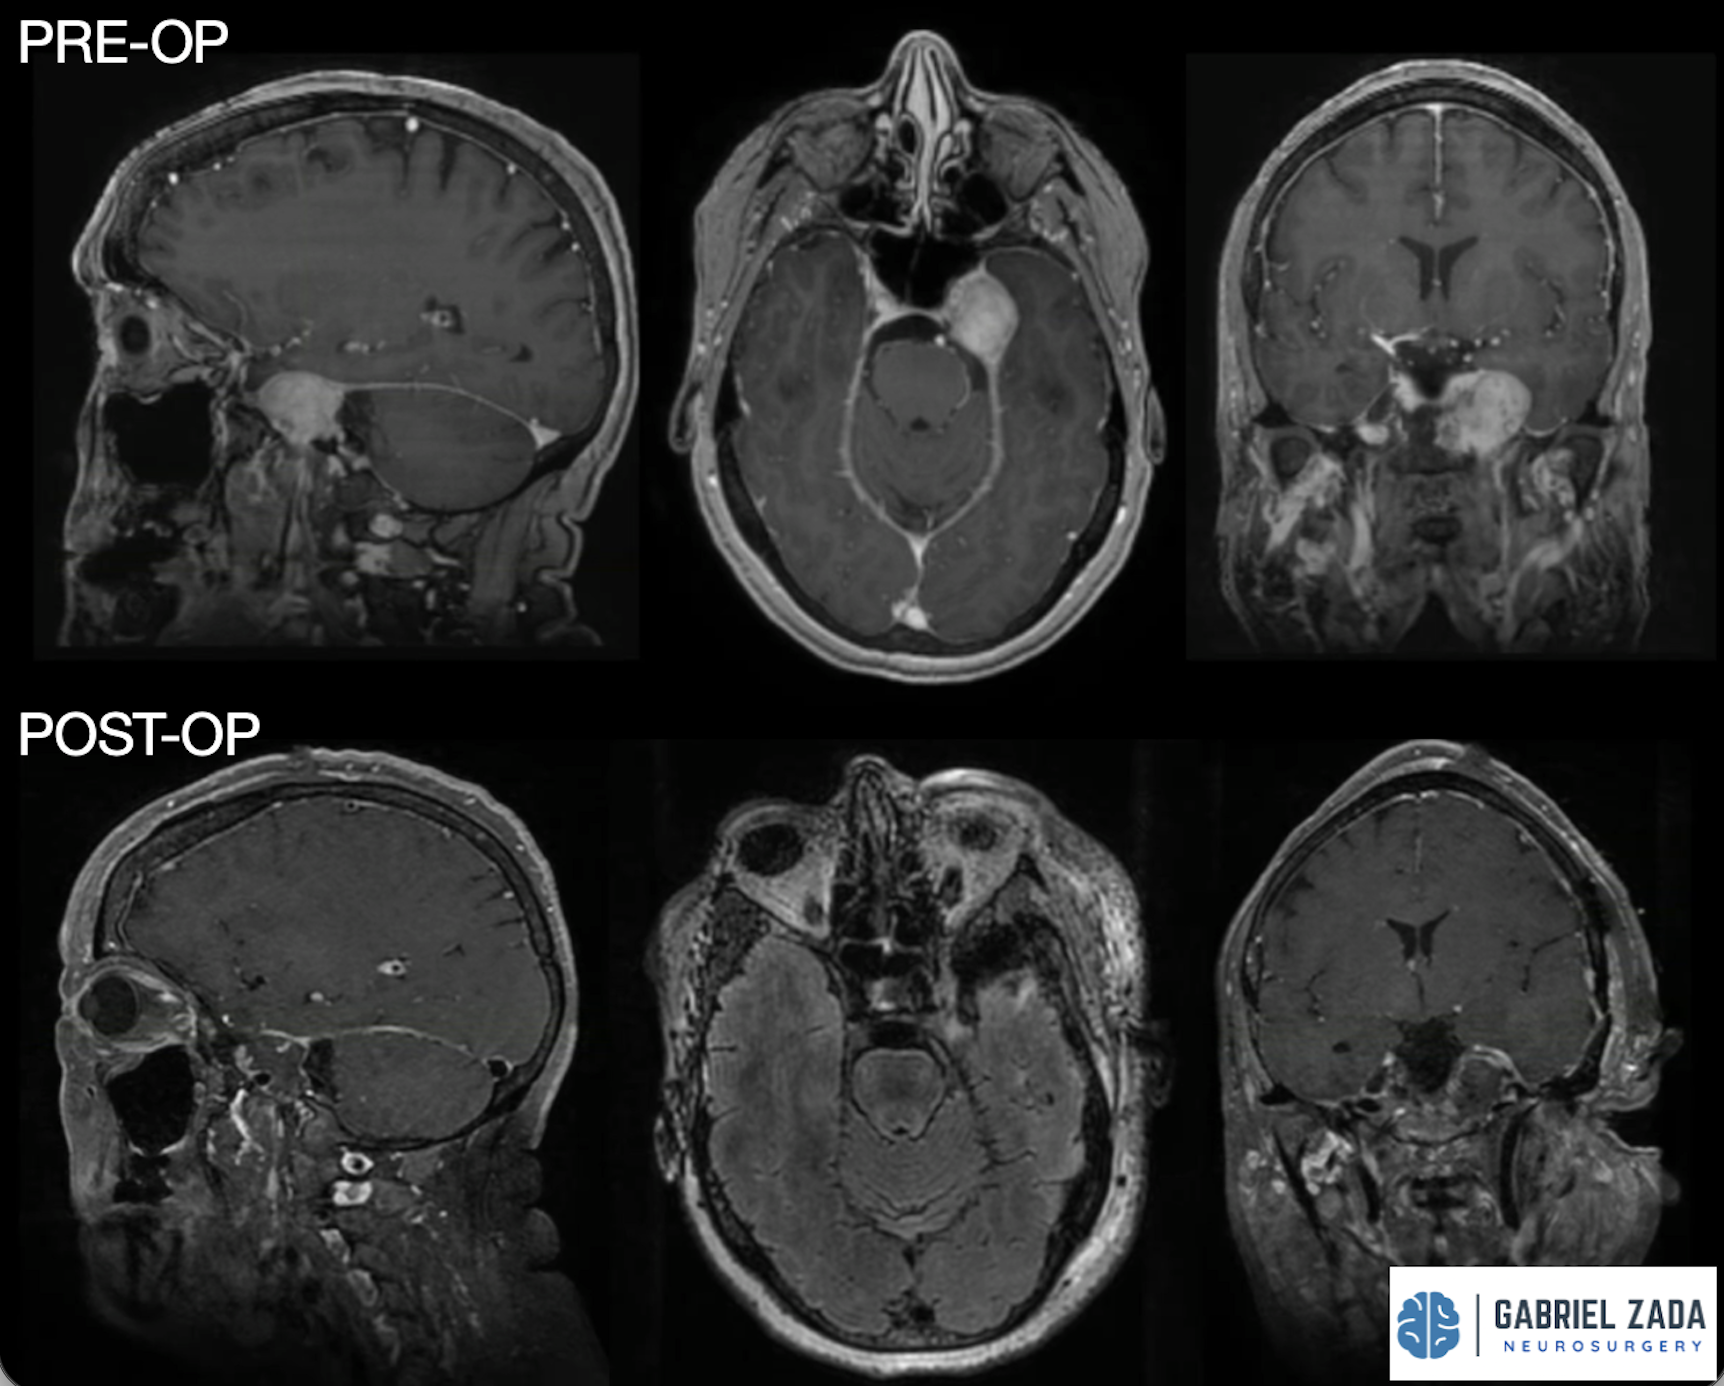

CHONDROSARCOMA surgery

Chordoma surgery treatment

Dr. Zada specializes in endoscopic endonasal approach (EEA) surgery, also known as transsphenoidal surgery, which allows surgeons to reach the pituitary gland through the nasal passages without making external incisions.